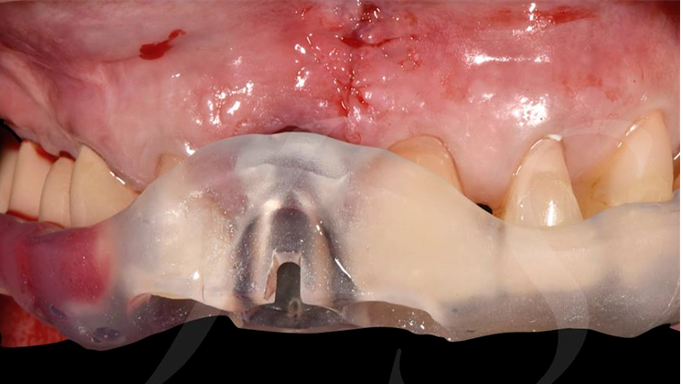

Clinical case: Extraction, immediate placement & loading using

R2GATE solution in aesthetic zone

- Courtesy of Dr. Jong-Cheol Kim, Korea-

“ One implant /One tooth/ One hour step-by-step

+ associated connective graft ”

Clinical case: EImmediate implant placement & loading of #35 extraction socket with defect

- Courtesy of Dr. Kwang Bum Park, Korea -